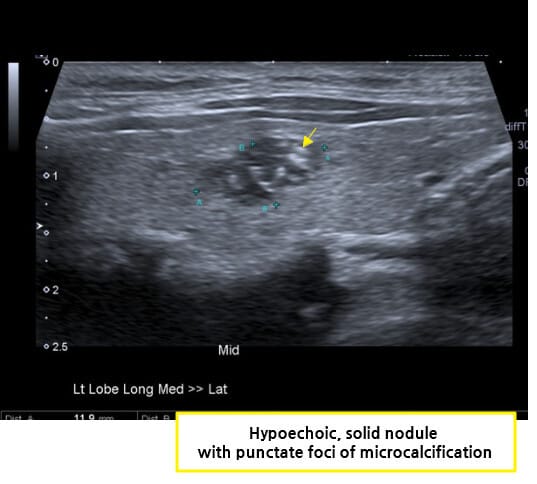

| 🔵 갑상선 초음파(Thyroid ultrasound) |

| 결절의 크기와 침습 여부를 평가합니다. |